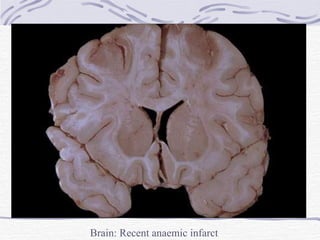

Ischaemic Stroke Infarction (stroke) Thrombotic – usually  anaemic  (may be haemorrhagic) Embolic – usually  haemorrhagic , often  multiple.  Haemorrhagic nature due to: Necrosis of vessel wall Lysis of embolus with restoration of some blood flow.

CNS Infarction Vascular occlusion causes: Necrosis of neurons, neuroglia and blood vessels 4-6 hrs. – coagulative necrosis 12-15 hrs. – sharp demarcation (swelling of neuropil) 24 hrs. – reactive changes Proliferation of microglia, astrocytes, capillaries Inflammatory reaction

CNS Infarction Infarction contd. 1-2 weeks – Swelling resolves Softening Shrunken granular grey matter Accumulation of lipid-laden phagocytes (gitter cells) in infarcted area Several months – shrunken cystic lesion traversed by glial fibrils and small blood vessels

Brain: Recent anaemic infarct